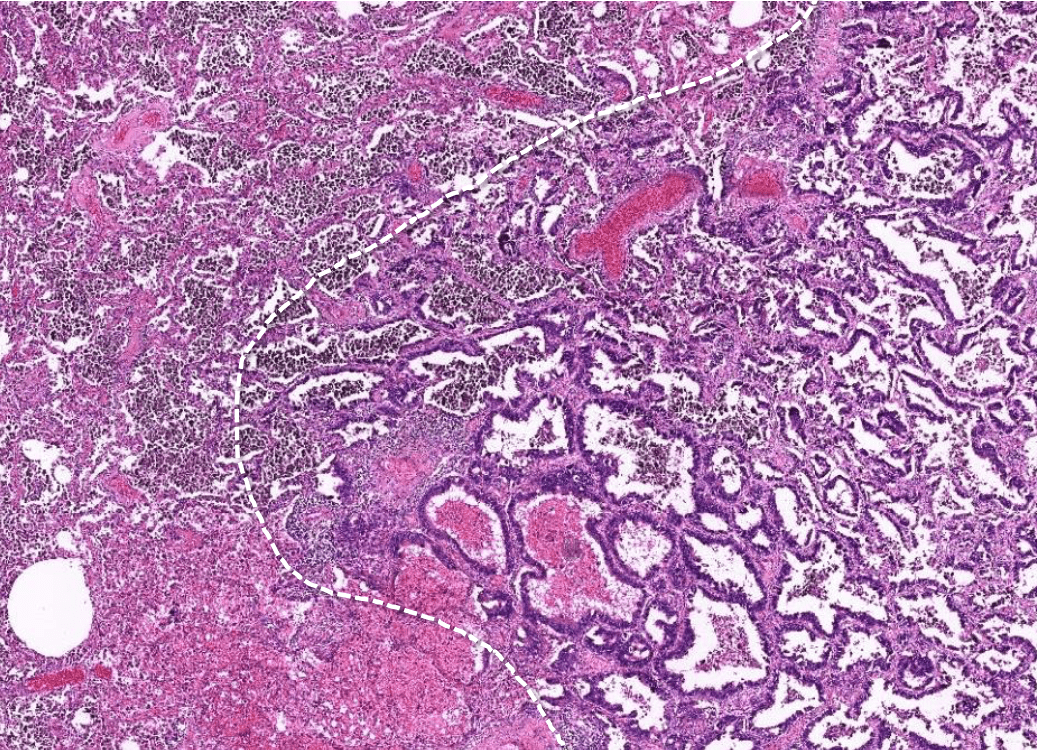

lung adenocarcinoma